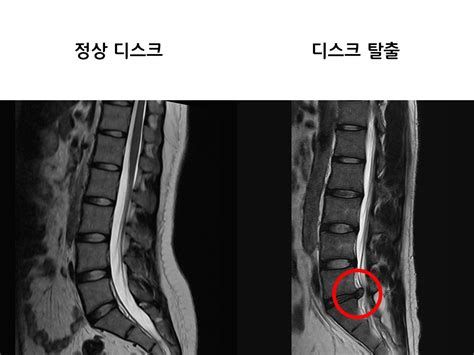

디스크(disc)는 척추뼈와 척추뼈 사이에 위치한 젤리 같은 물렁뼈 조직으로, 우리말로는 추간판이라고 부릅니다. 이 조직은 척추뼈끼리 직접 부딪히는 것을 막아주는 쿠션 역할을 하며, 척추의 움직임을 부드럽게 하고 외부 충격을 흡수하는 기능을 담당합니다.

디스크에 과도한 힘이 가해지거나 노화 등으로 인해 섬유륜이 손상되면, 내부의 수핵이 밖으로 튀어나올 수 있습니다. 이때 튀어나온 수핵이 신경을 압박하여 통증이나 감각 이상, 심하면 마비 증상까지 유발할 수 있는데, 이를 흔히 **허리디스크(요추 추간판 탈출증)**라고 부릅니다.